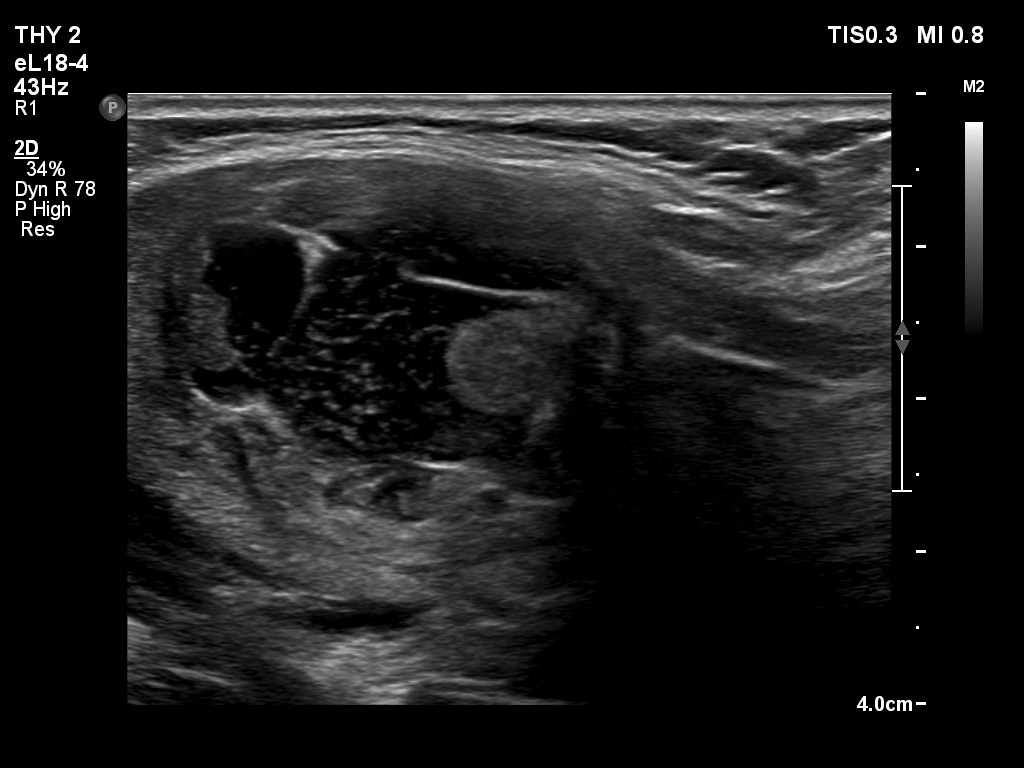

Ultrasonography. The thyroid was echonormal. The right lobe contained several discrete areas without any clinical significance. There was multi-chambered cystic nodule in the left lobe. The nodule had echonormal solid part and presented halo sign.

- The distinction between a multi-chambered cyst and a spongiform cyst is important, because in the latter the risk of malignancy is practically zero. In spongiform cysts almost the entire nodule is composed of cystic areas, and there is very small proportion of solid areas.

- The cyst has just started refilling after the evacuation.